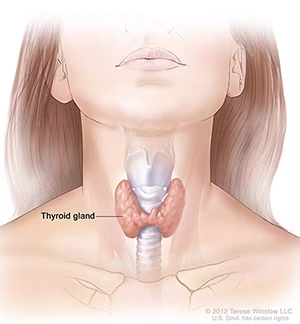

🧠 مشکلات تیروئید در هفته دوازدهم بارداری

غده تیروئید مانند موتور بدن عمل میکند و در دوران بارداری نقش حیاتی در رشد مغز و متابولیسم جنین دارد.

گاهی در این دوران ممکن است مادر دچار کمکاری یا پرکاری تیروئید شود.

🔹 کمکاری تیروئید (هیپوتیروئید):

باعث خستگی، خوابآلودگی، افزایش وزن و خشکی پوست میشود.

🔹 پرکاری تیروئید (هایپرتیروئید):

ممکن است موجب تپش قلب، بیخوابی، کاهش وزن و اضطراب شود.

علائم این بیماریها میتواند مشابه علائم طبیعی بارداری باشد، بنابراین انجام آزمایش خون بسیار مهم است.

اگر تیروئید درمان نشود، میتواند باعث زایمان زودرس، پرهاکلامپسی یا کاهش وزن جنین شود.

✅ خبر خوب: درمان تیروئید در بارداری ایمن است. پزشک متخصص زنان و زایمان ممکن است داروهایی برای تنظیم سطح هورمون تجویز کند و هر شش تا هشت هفته آزمایش کنترل انجام دهد.